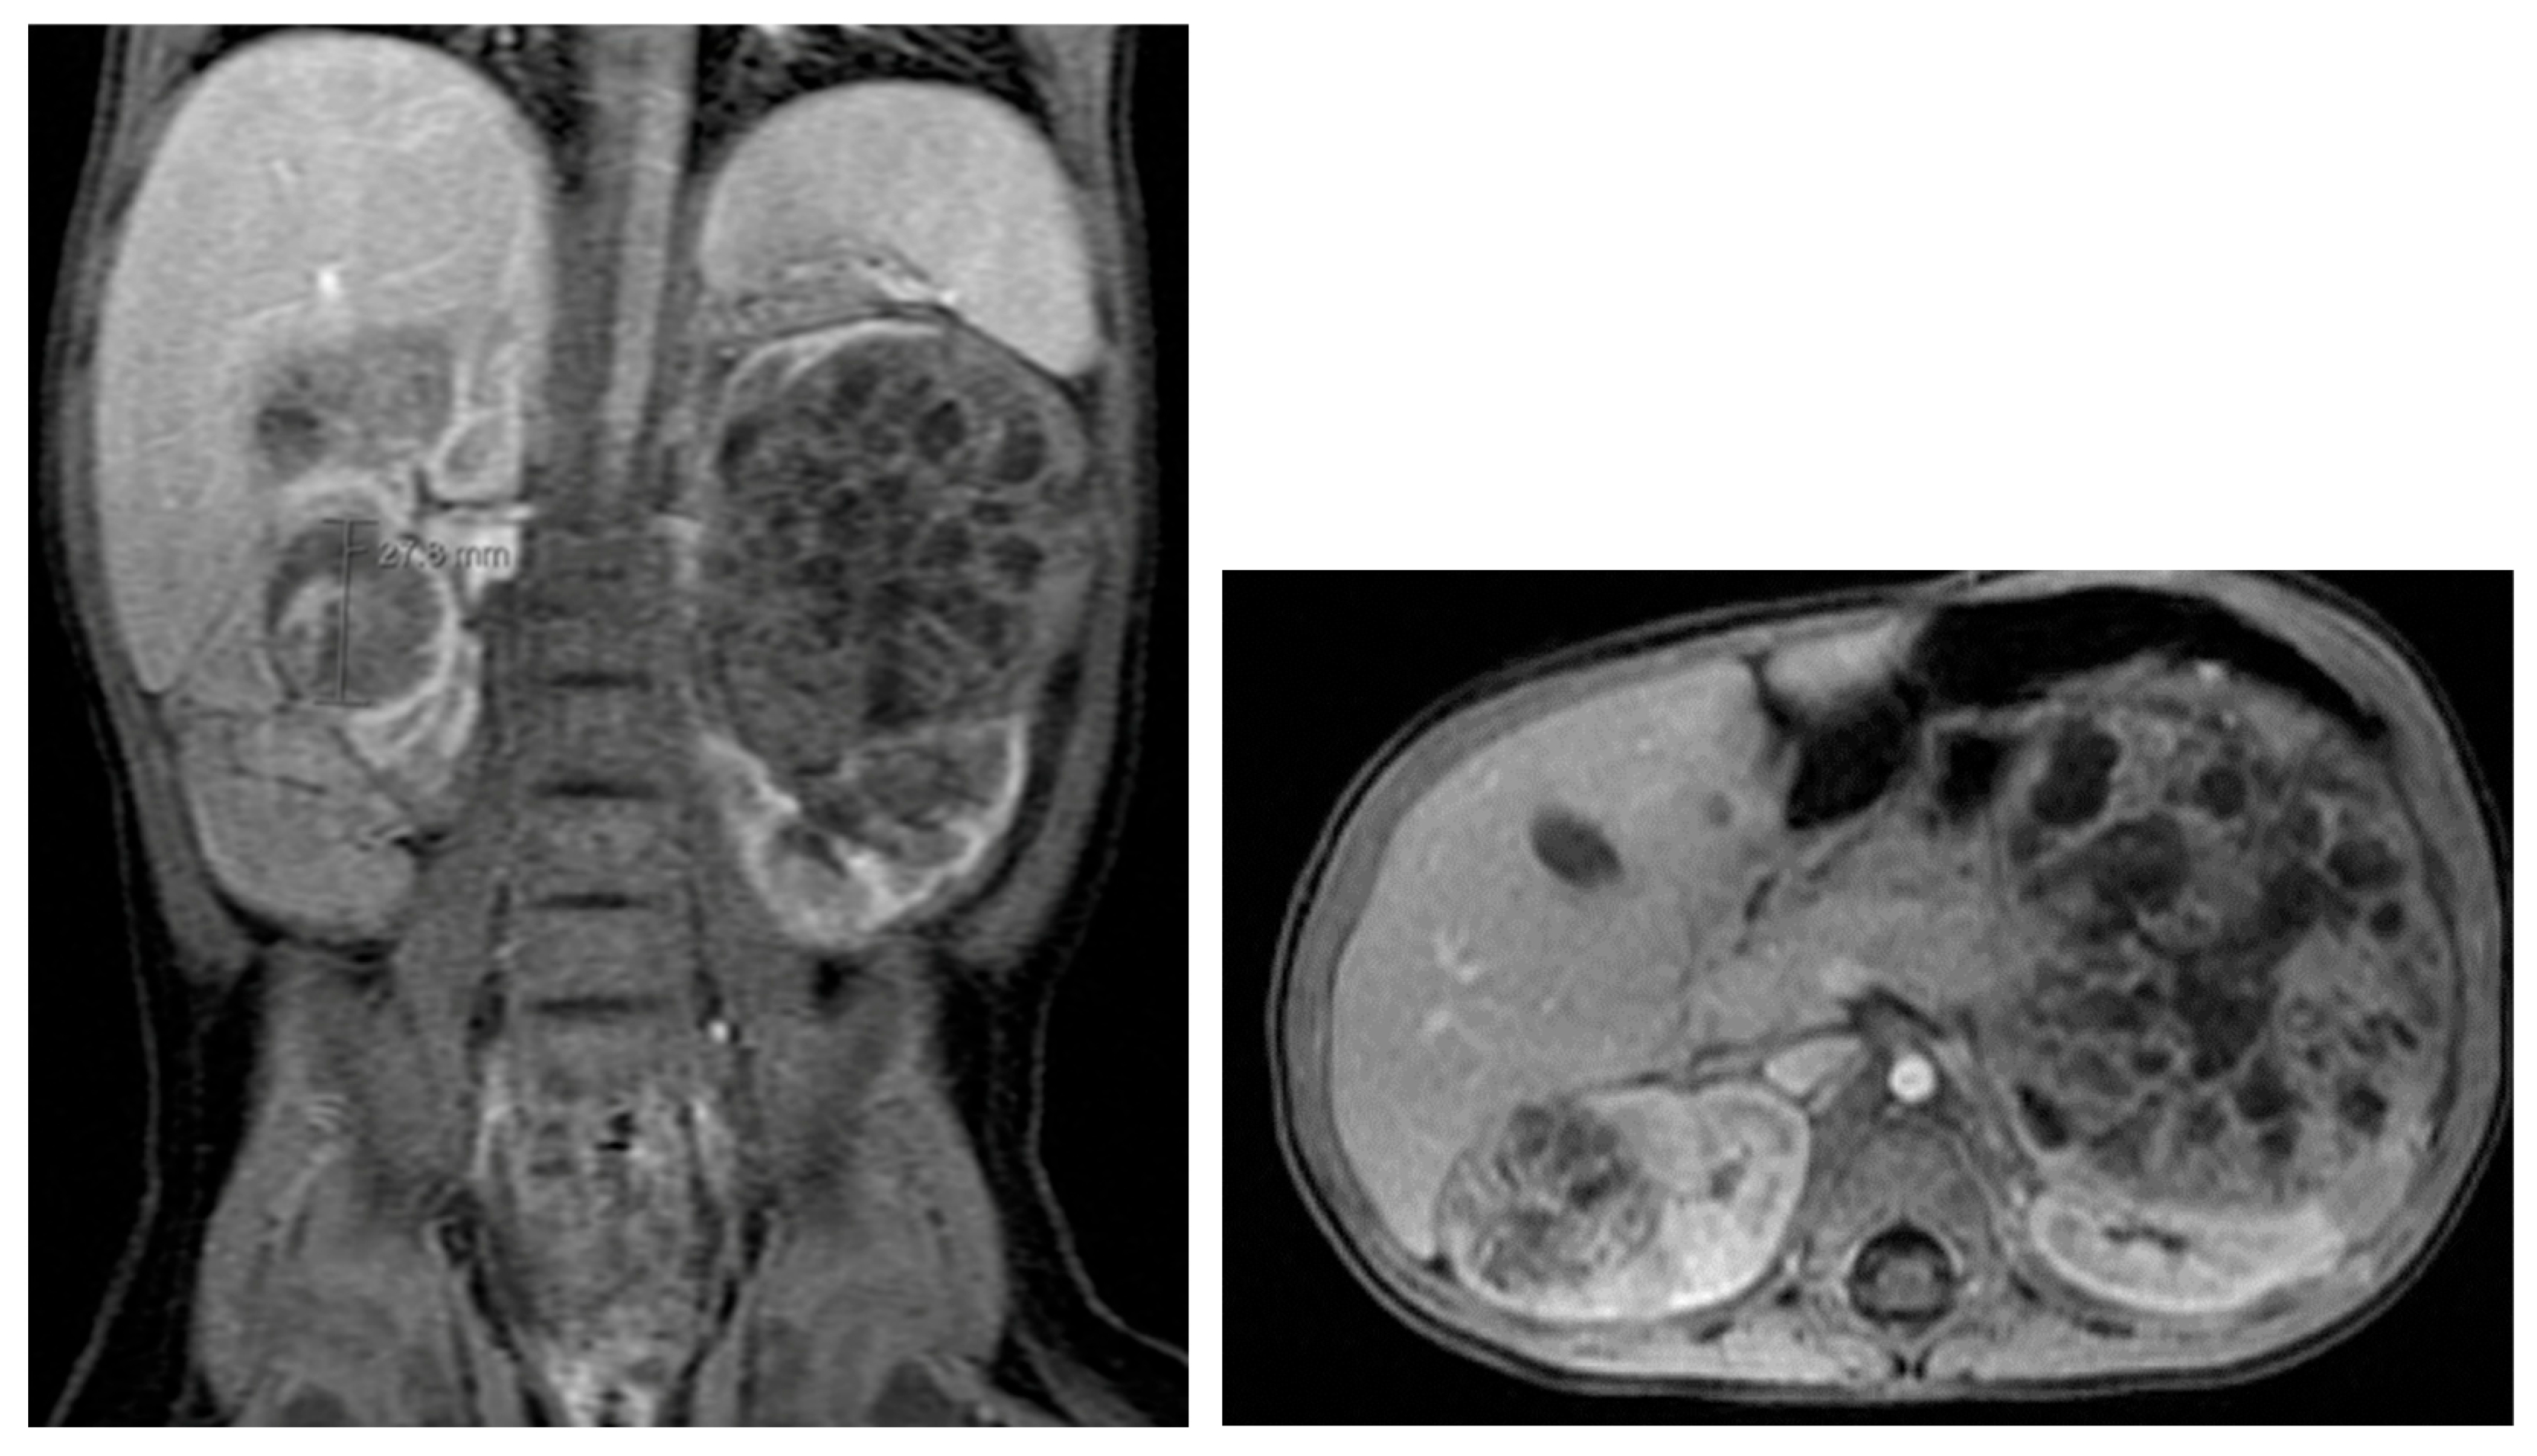

12. Multicystic Dysplastic Kidney (MCDK)

17. Cystic Kidney Disease